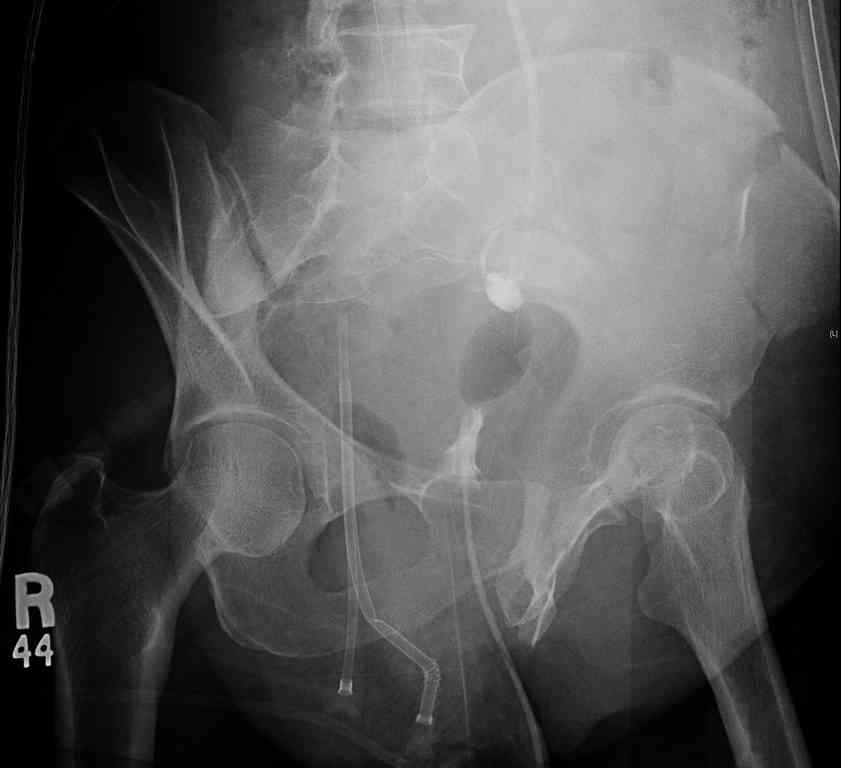

comminuted crescent fx

Ортопедия и травматология Отправлено Jeff Richmond 25 Сентябрь 2007, 22:43

Any advice would be appreciated:

40 ish female ejected from car. Unstable, DPL negative, went to angio and had her pelvic bleeds embolized after many units of blood. GCS 6, floating elbow, clavicle, bothbones, etc.

My standard approach to this pelvis would be posterior, reduce/lag/plate thecrest, reduce/plate the caudal extent on the posterior crest and 1-2 lags back to front. In this case, the crest comminution seems to make plating all the way to the ASIS useless, as the plate would be on free floating fragments. Would plating the posterior extent of the fracture to secure the reduction at the SI joint and 2 screws back to front be sufficient fixation? Would anyone do a perc reduction and perc back to front screws, and would that be sufficient if the SI joint could be reduced (although I don't see how this could be accurately reduced closed). Would an ilioninguinal with a pelvic brim plate and posterior column screws be a better approach, although reducing the SI would be more indirect and less accurate?

It's a comminuted iliac fracture involving the GS notch and all that

implies...use the lateral interval of an ilioinguinal, sequentially reduce,

and fix...if you want to, you can attach the dominant unstable fragment to

both the stable posterior iliac fragment and also to the anterolateral portion of the sacrum using plates...if you choose to anchor to both, the implants get congested on the iliac side of the SI joint so be precise with contouring and such applications...perhaps and based on the images shown, an iliosacral screw would only augment the construct if applied to the second sacral segment (but this is difficult to assess on the images shown). The crest components can be held securely with screws and/or peripheral plating.